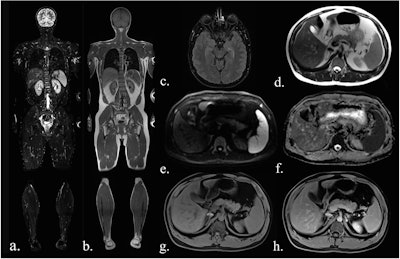

Examples of false-positive findings: Contrast-enhancement in the T1 Dixon water-only image of the pharyngeal wall (white arrow in a) was confirmed as regular hyperplastic pharyngeal tissue on biopsy. A focal contrast-enhancement of the gastric wall (white arrow in b) was no longer detectable on follow-up MRI (c) and was retrospectively deemed an artifact.